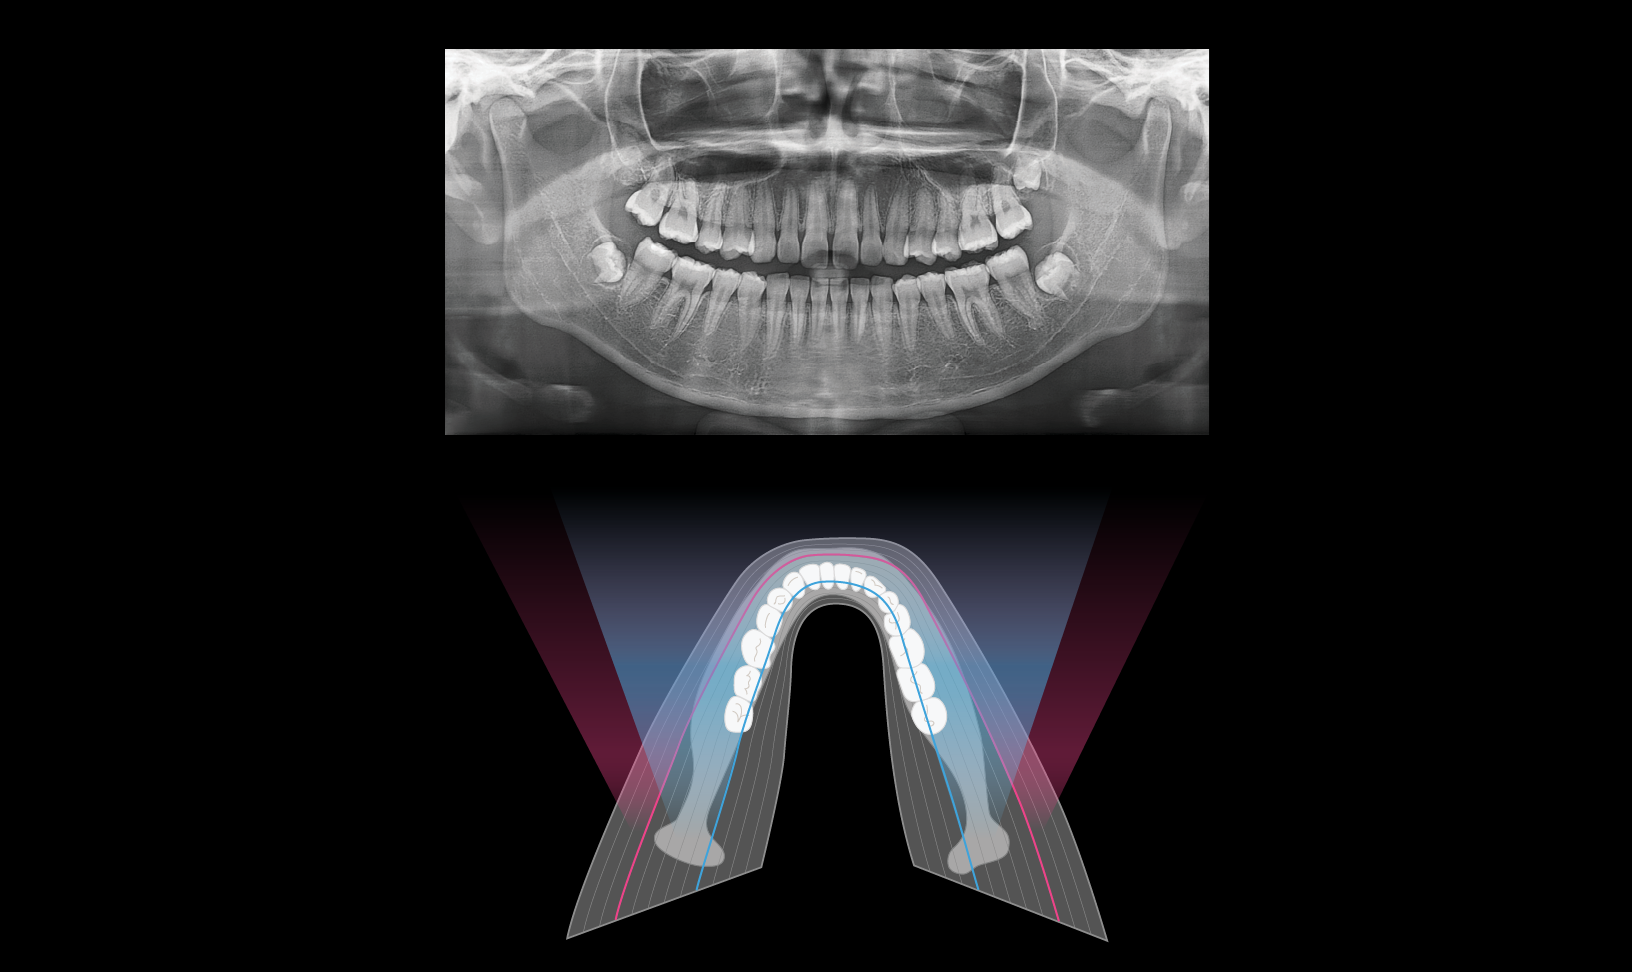

Clear panoramic image

The AMF (Adaptive Moving Focus) technology selects the optimal image layer to provide clear panoramic images, allowing for easy identification of the patient’s periodontal condition and lesion locations.

Clear panoramic image

The AMF (Adaptive Moving Focus) technology selects the optimal image layer to provide clear panoramic images, allowing for easy identification of the patient’s periodontal condition and lesion locations.